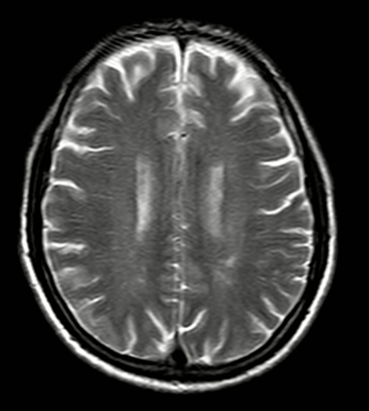

CASE LÂM SÀNG: CHẨN ĐOÁN BỆNH NHÂN MẮC HAI UNG THƯ: GIST RUỘT NON VÀ UNG THƯ TUYẾN GIÁP TẠI TRUNG TÂM Y HỌC HẠT NHÂN VÀ UNG BƯỚU, BỆNH VIỆN BẠCH MAI

Ca lâm sàng